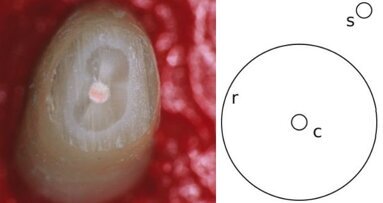

OSLO, Norveška / HELSINKI, Finska: Krone iz nerjavečega jekla se priporočajo za obnovitveno zdravljenje zob mladih pacientov, ki so močno prizadeti ...